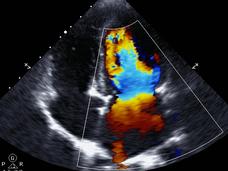

Doxorubicin is used to treat many types of childhood cancer, but it can damage the heart. Giving dexrazoxane (Zinecard) before each dose substantially decreases a child's risk of treatment-related heart problems in adulthood, new study results show.